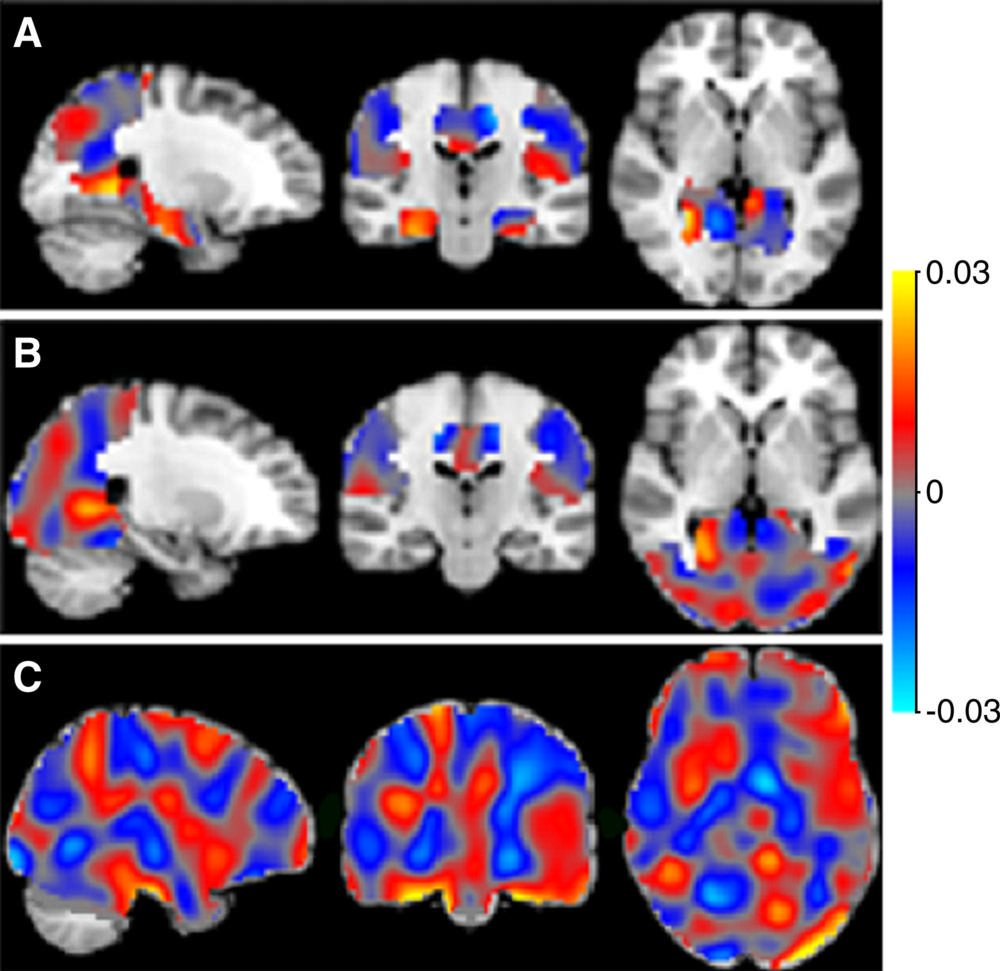

Figure 1. Researchers applied machine learning methods to special type of MRI called arterial spin labeling imaging to distinguish different stages of Alzheimer's disease.